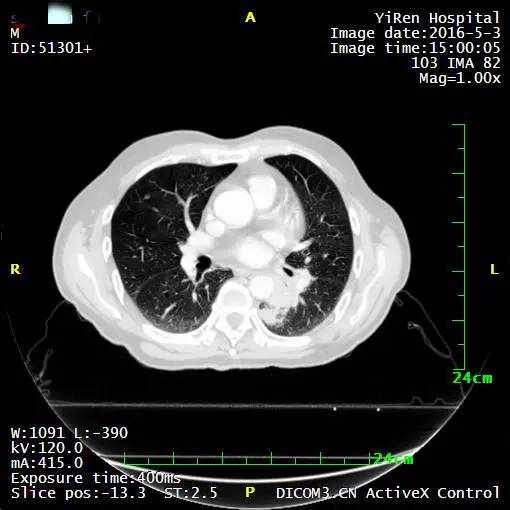

2、患者男性,64岁,小细胞肺癌

2016年3月,王先生因咳嗽加重就诊于当地医院,支气管镜病理检查提示:考虑小细胞癌的可能性大。

化疗一周期,病情无改善症状加重。

2016年4月,王先生接受了A45治疗,一个月后复查,病灶明显缩小,2016年7月复查,病灶进一步缩小,由于A45治疗具有明显的远观效应,能够激发自身的免疫系统,长期有效的消灭体内肿瘤,2016年12月,王先生肺部病灶几乎全部消失。

治疗前

治疗后